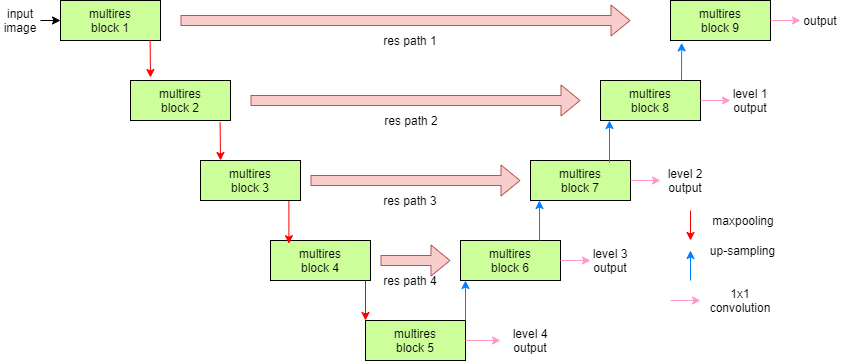

MultiResUNet

The generic design of this network is quite similar to that of U-Net, except for slight differences in the nature of convolutions in each layer and the residual path from the encoders to the decoders (Figure 2). Each layer of U-Net is replaced by a MultiRes block that contains 4 convolutions (Figure 2(b)). The skip connections of U-Net are replaced by Res Paths (Figure 2(c)) as described in [25]. The motivation of adopting this network comes from the idea that an ideal architecture should be able to assess images having diversified scales in medical image segmentation procedures. For further details readers are referred to [25].

(a) Network architecture

(b) MultiRes block

(c) Res Path Figure 2: MultiResUNet architecture. Figure borrowed from [25]. -